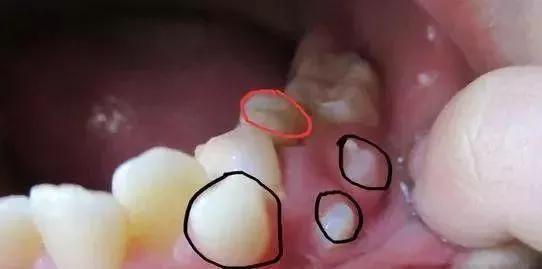

家长要留意孩子的乳牙和恒牙的生长情况,定期去看牙医,以便发现问题及早解决。家长如果发现乳牙旁边有恒牙长出,但乳牙未脱落,形成了双排牙,这时家长要尽早带孩子去医院拔除滞留的乳牙。另外,如果上颌门牙缝隙过大、畸形牙齿从上门牙位置长出、一颗门牙从异常位置长出,这说明可能有一个地方长多颗牙齿的情况,要到医院就诊。